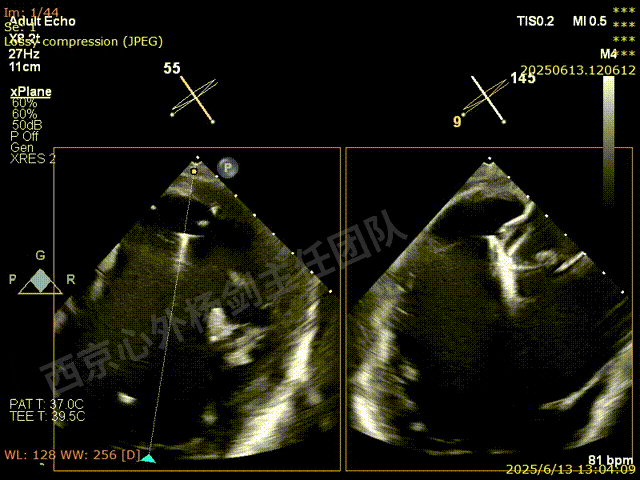

第一枚XTW在2区弹道测试调整

第一枚XTW打开确认orientation,穿刺位置良好无需调整hug

XTW进入瓣下,以较小的角度先捕捞后叶

反复尝试,瓣叶卷曲,前后瓣叶不明确